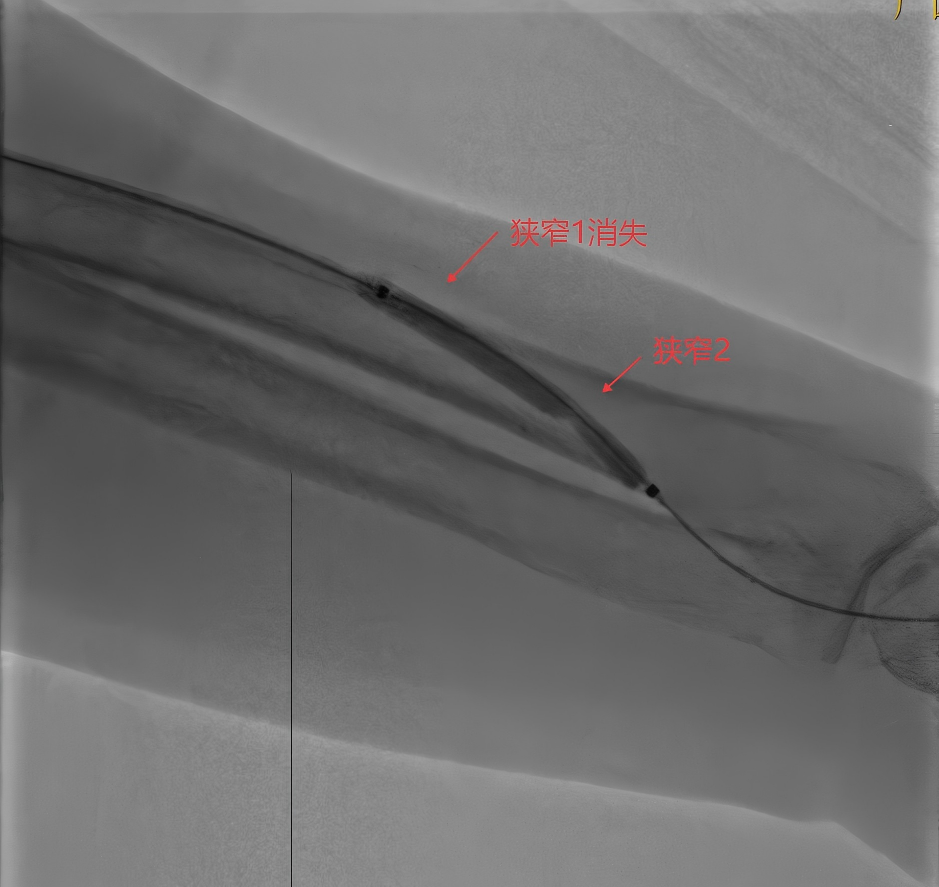

解除第一个腰

解除第二个腰